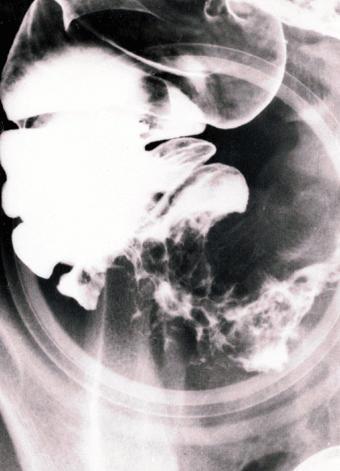

伴有微小胃病变的小肠、大肠克罗恩病的切除病例

Tokyo Pref., 国立癌中心中央病院和九州癌中心共同完成

炎症性・溃疡性疾患/克罗恩病

大肠/回盲部

X线